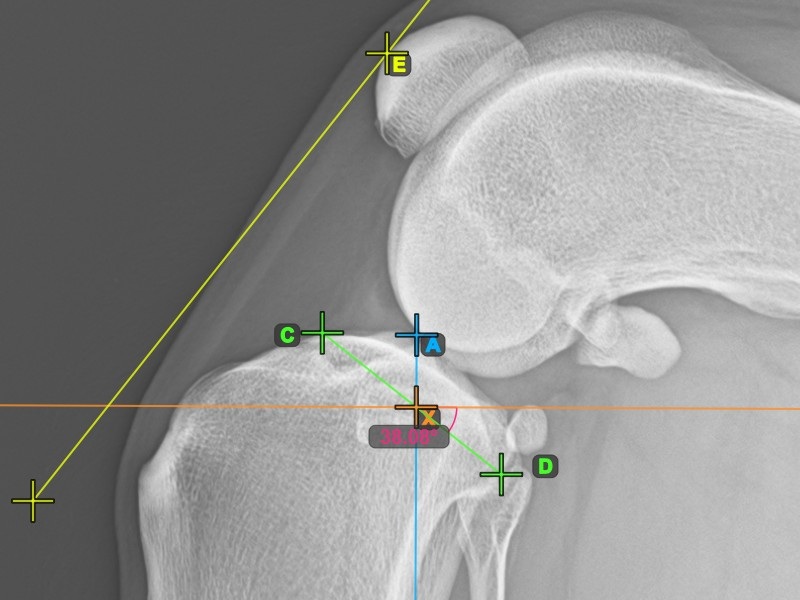

A lenti kép a tibia plató legalacsonyabb pontjának szokásos elhelyezkedését és az automatikusan kiszámított TPA szög mérését ábrázolja.

Fejezze be a TPA szög mérését a tibia fejének (tibia plató) legalacsonyabb pontjának megjelölésével. A TPA szög automatikusan kiszámításra kerül a tibia platón lévő két pontot összekötő vonal és a tibia hosszanti tengelyére merőleges vonal közötti szögként.